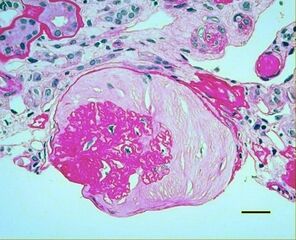

| Micrograph showing renal arterial hyalinosis – pink ring right-of-centre. PAS stain. | |

In the kidneys, as a result of benign arterial hypertension, hyaline (pink, amorphous, homogeneous material) accumulates in the walls of small arteries and arterioles, producing the thickening of their walls and the narrowing of the arterial openings, a process known as arteriolosclerosis. The resulting inadequate blood flow produces tubular atrophy, interstitial fibrosis, and glomerular alterations (smaller glomeruli with different degrees of hyalinization – from mild to sclerosis of glomeruli) and scarring around the glomeruli (periglomerular fibrosis). In advanced stages, kidney failure will occur. Functional nephrons[6] have dilated tubules, often with hyaline casts in the opening of the tubules. Additional complications often associated with hypertensive nephropathy include glomerular damage resulting in protein and blood in the urine.[citation needed]

In benign nephrosclerosis, the changes occurring are gradual and progressive, however, there can be sufficient kidney reserve capacity to maintain adequate kidney function for many years.[10] The large renal arteries exhibit intimal thickening, medial hypertrophy, duplication of the elastic layer. The changes in small arterioles include hyaline arteriolosclerosis (deposition of hyaline, collagenous material),[citation needed] which causes glomerular collapse (wrinkling and thickening of capillary basement membranes and collapse of capillary lumen) and solidification (glomeruli exhibit sclerosis and increase in mesangial matrix). The degree of scarring correlates with the degree of glomerular filtration deficit.[citation needed]